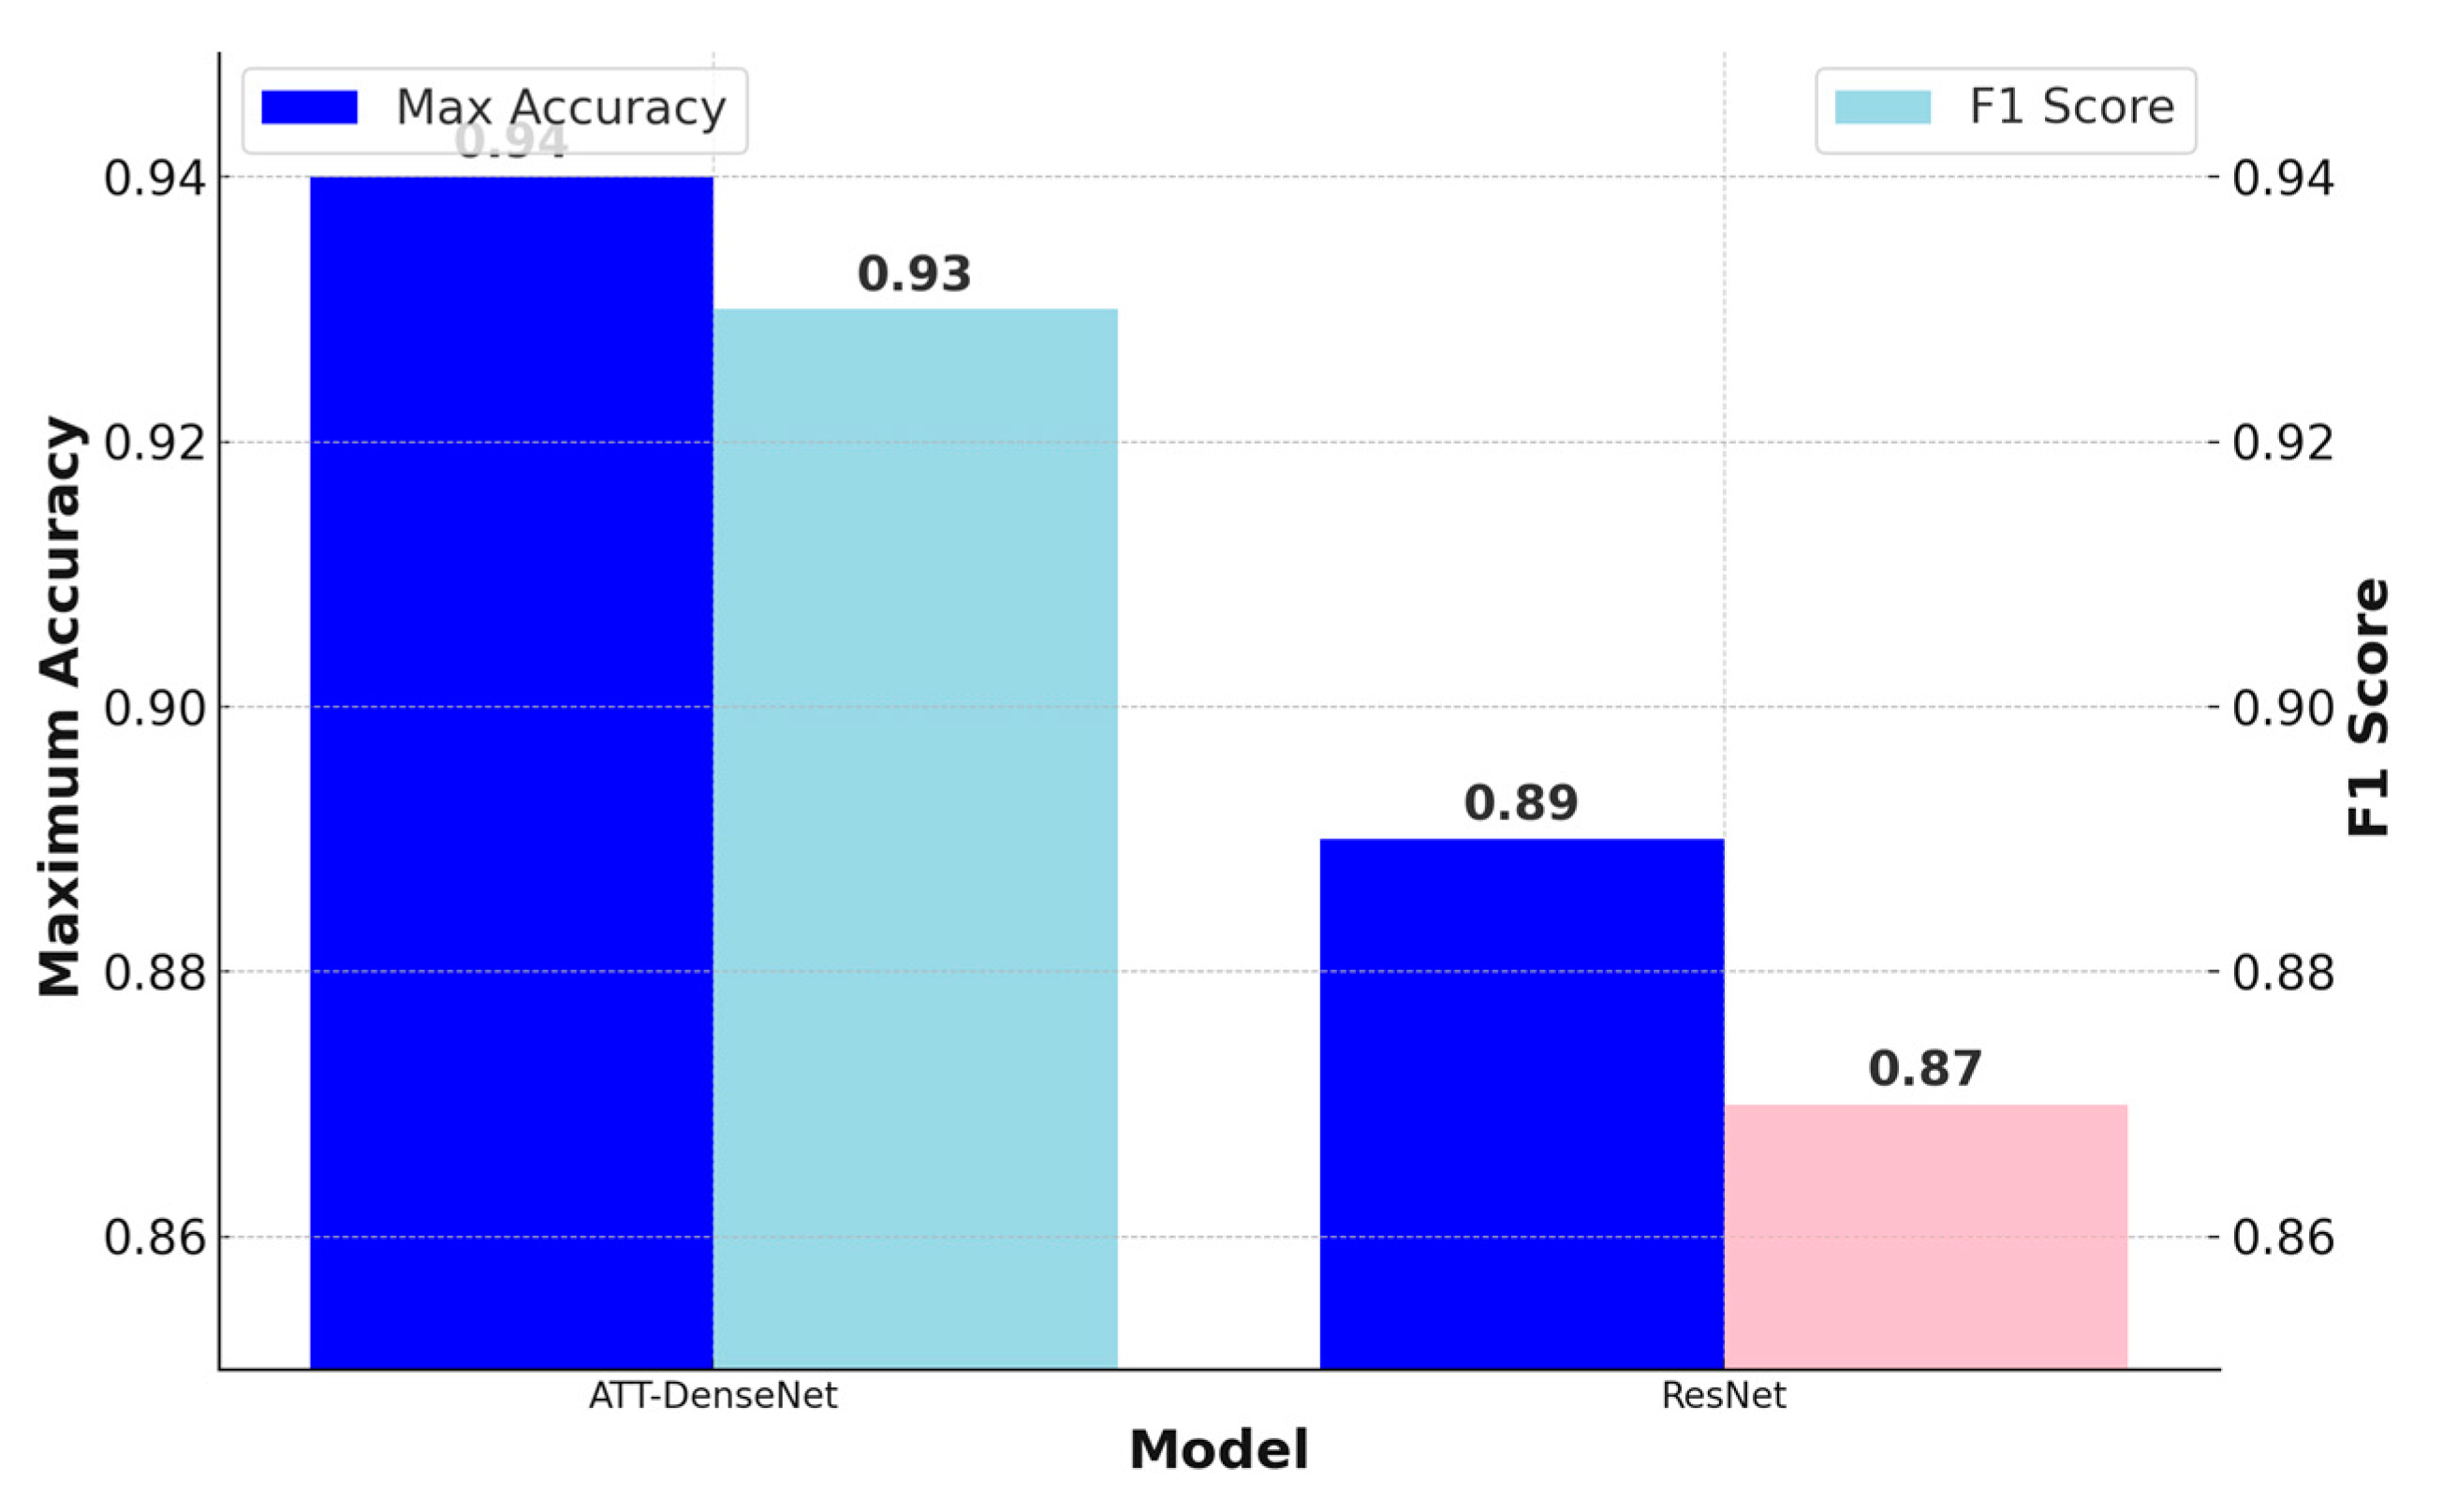

Figure 10 presents an accuracy curve comparison.

We can see from

Figure 10 that the proposed ATT-DenseNet achieves higher accuracy compared to all the baselines by achieving 94% average accuracy on the test set of the data. Similarly, as presented in terms of histopathological images, the F1-score of ATT-DenseNet is found to be higher than all the other baselines for CT scan images. Finally, we compare the proposed method with RestNet in terms of accuracy and the F1-score and see that the proposed method performs better as well.

The proposed ATT-DenseNet mechanism adaptively recalibrates feature responses by explicitly modeling interdependencies between channels. This means that the method can dynamically emphasize informative features while suppressing irrelevant ones. By contrast, DenseNet without attention, SqueezeNet, and AlexNet lack such mechanisms to focus on the most relevant features, potentially leading to suboptimal feature utilization. Furthermore, the proposed ATT-DenseNet facilitates better discrimination of features by learning channel-wise relationships. By selectively emphasizing important features, the method can potentially enhance the discriminative power of the network, leading to improved classification performance. DenseNet without attention, SqueezeNet, and AlexNet do not have the capability to learn such discriminative features effectively. The adaptive nature of ATT-DenseNet allows the method to dynamically adjust feature importance based on the input, leading to improved generalization across the datasets and scenarios. This adaptability enables our model to capture complex patterns in the data more effectively compared to the fixed feature mappings of DenseNet without attention, SqueezeNet, and AlexNet. DenseNet’s dense connectivity pattern enables feature reuse throughout the network, leading to parameter efficiency. This means DenseNet requires fewer parameters compared to ResNet or traditional architectures to achieve similar or better performance. With fewer parameters, DenseNet models can be trained faster and require less memory. DenseNet’s dense connections facilitate a direct gradient flow from the later layers to the earlier layers during backpropagation. This helps alleviate the vanishing gradient problem, making it easier to train very deep networks. That is why, as presented in

Figure 11, we achieved better accuracy for the proposed ATT-DenseNet.